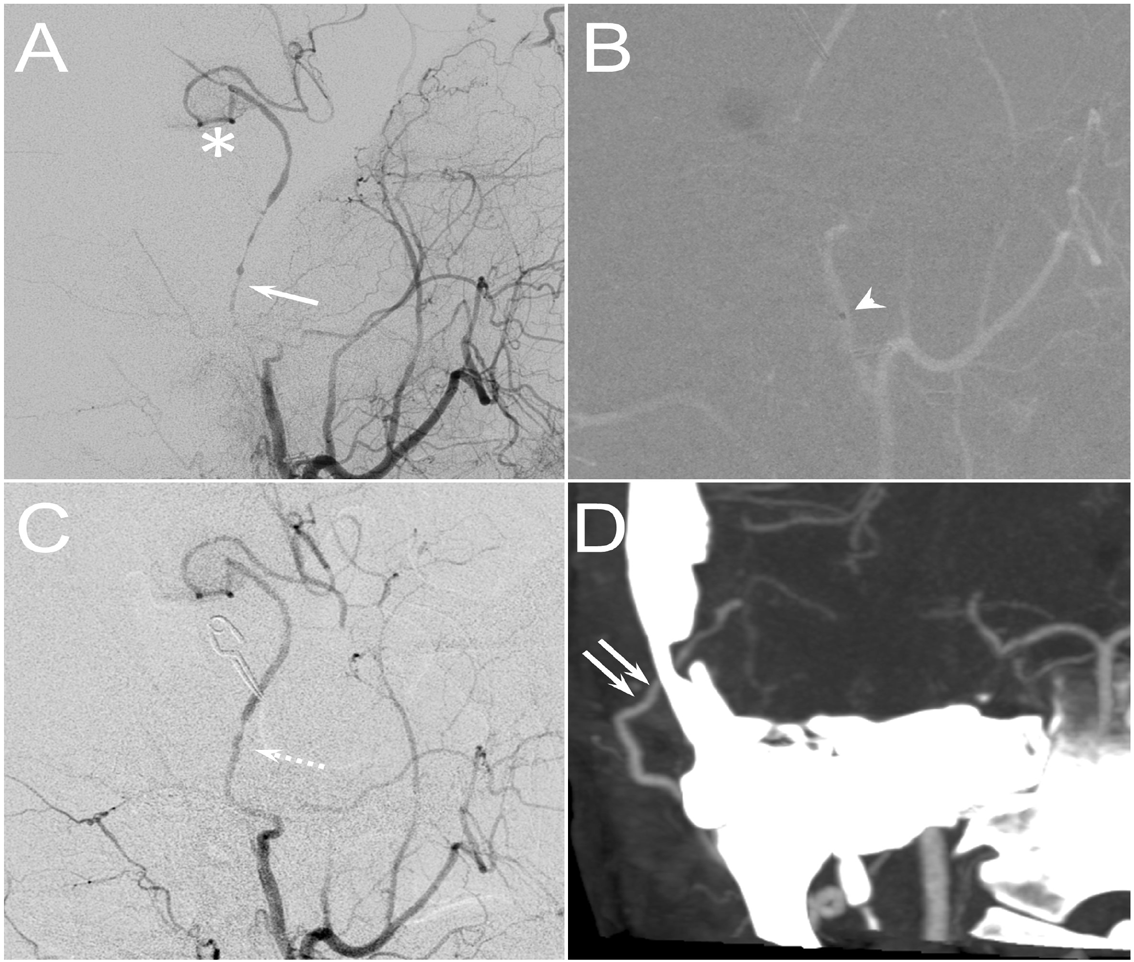

Figure 2: (A) Intraoperative angiogram demonstrated a patent bypass graft (star sign) but a severe vasospasm of the STA pedicle (arrow). (B) The microcatheter tip (arrowhead) was placed in the beginning of the STA pedicle, and after intra-arterial nimodipine infusion, the vasospasm significant relieved (dashed arrow). (D) The bypass graft remained patent as demonstrated by follow-up CTA one month after the surgery (double arrows).